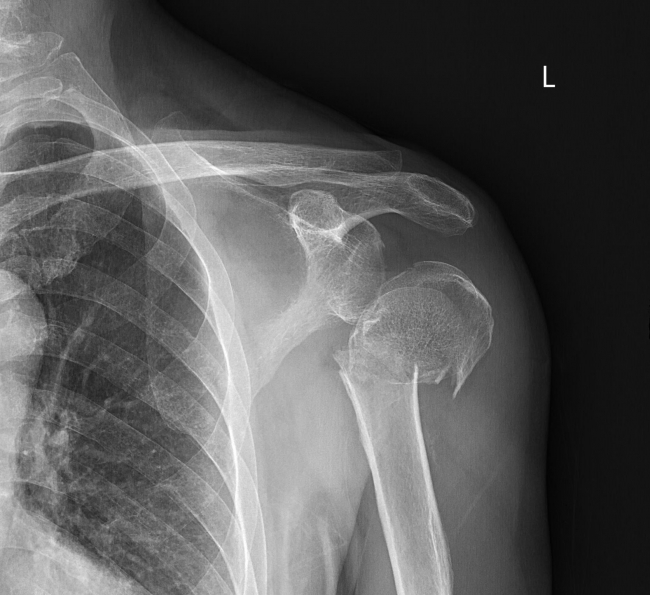

近日, 68岁的朱大叔,因不慎摔伤导致右肩部疼痛伴活动受限,来到湘南学院附属医院就诊,经检查诊断为“左肱骨外科颈粉碎性骨折,Neer 分型IV、肩关节半脱位”后收入骨一科进一步治疗。

(术前左肩关节CT片)